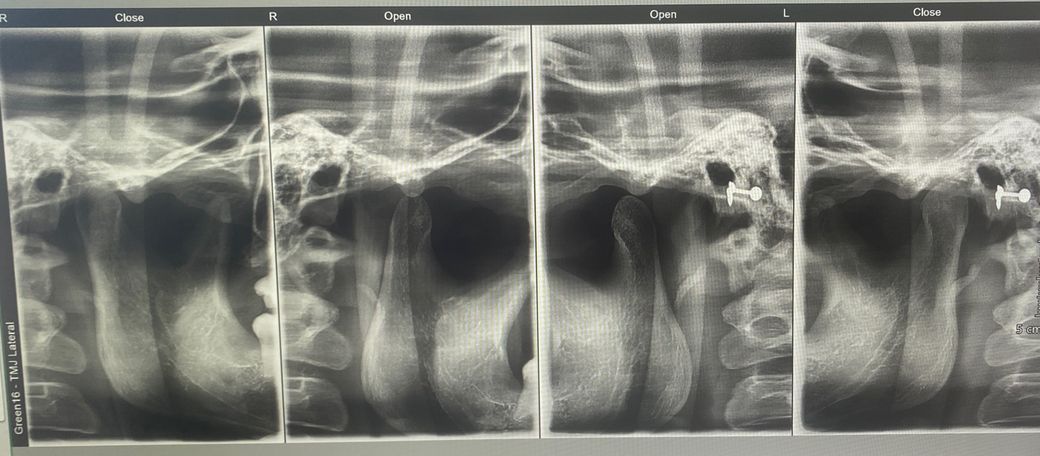

턱관절이 뒤로 밀린건지, 관절 내 공간이 좁은지, 뼈가 갈렸는지, 턱관절 모양 자체가 불리하다던지 등등.. 문제가 있을까요

사진은 같은 날 찍은게 아니고 2달정도의 날짜 간격이 있습니다. 둘다 턱관절 증상 있을 때입니다

제가 보기엔 오른쪽 관절 내 공간이 더 좁고, 하악도 오른쪽이 더 뒤로 들어가있는건 맞는 것 같거든요..

근데

왼쪽도 위치 상의 문제가 있는지도 궁금하고

과두 모양도 오른쪽이 더 얇아진 것 같은데 ..

• 3번 째 사진

• 4번 째 사진